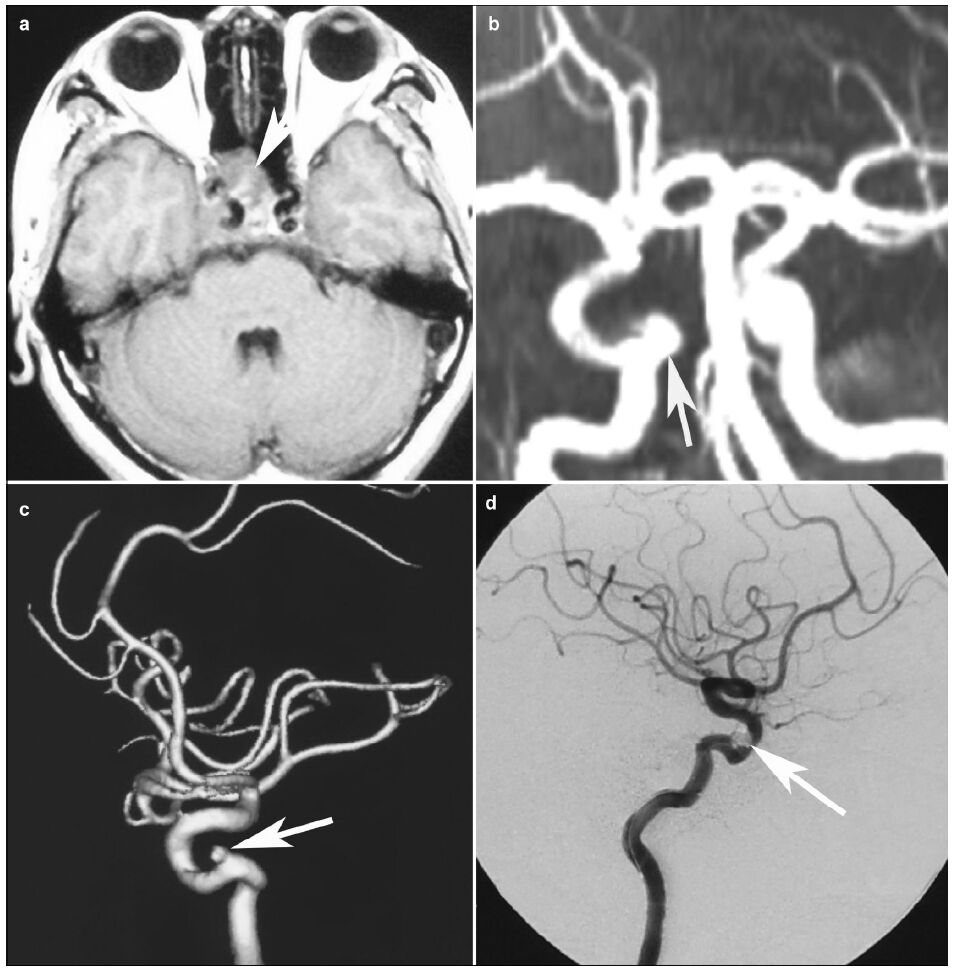

2 Case presentationPatient: male, 55 years old, suffered from sexual dysfunction for 2 years. Physical examination showed no positive signs. MRI showed a lesion located at the sellar area, and the tumor invaded the right cavernous sinus (Figure 1a). The serum prolactin was tested as 1, 600ng/ml (normal range, 1.39-24.2ng/ml). Prolac-tinoma was diagnosed. And he took bromocriptine for 3 times a day, with a dose of 2.5mg/time. One year later, cranial MR showed no evident changes in the tumor size, although the level of serum prolactin decreased to 46.3 ng/ml. He then took the gamma knife therapy to inhibit the growth of tumor. Four months after the gamma knife therapy, he got some clear liquid flowing out of the nasal cavity when bowing his head. The liquid was tested, showing Glu: 2.7mmol/L (range 2.5-4.5 mmol/L). Therefore, the patient was diagnosed with CSF rhinorrhea. After admission, he got the nasal bleeding. The blood amount was about 30ml, and the bleeding stopped thereafter. At first, the nasal bleeding was ignored. We chose endoscopic transnasal- sphenoidal approach to resect the tumor and repair the dura defect in the diaphragma sellae. The tumor apoplexy was not found during the operation. The dura defect was repaired, and the rhinorrhea stopped after the operation. However, he got another serious epistaxis 3 months after the operation. The bleeding was stopped with stuffing and compression. A suspi-cious aneurysm of right cavernous internal carotid was found in the MRA (Figure 1b), and the aneurysm was confirmed by the digital subtraction angiography DSA (Figure 1c). The endovascular coil embolization was performed to treat the aneurysm (Figure 1d). After the endovascular treatment, the patient was completely cured and discharged. During the follow-up of next two years, he recovered well and reported no new complaints.

| Figure 1 MRI and DSA of the patient. a: MRI shows a lesion locating at the saddle area and invading right cavernous sinus (arrow).b: The MRA 4 months after gamma knife shows a suspicious aneurysm (arrow). c: Three-dimensional DSA confirms the existence of the aneurysm (arrow). d: DSA image after the embolization shows that the treatment effect is satisfactory (arrow). |